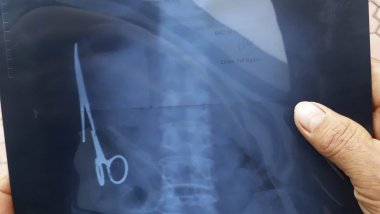

Taguri: no comment SHOCKING moment Florida woman ALLOWS a snake to bite her ONE-YEAR-OLD daughter (VIDEO) Meet the ink-addict covered HEAD-TO-TOE in $100,000 worth of tattoos including one on his EYEBALL (PHOTO/VIDEO) Man has scissors removed from inside him after 18-year stomach ache NO COMMENT! Man punches kangaroo in face in order to save his pet Felix the Huddersfield station cat given promotion in recognition of her mouse-catching skills NO COMMENT: Trump supporter leaves anchor speechless during interview Extraordinary photographs show very rare wavelike clouds 1 ABCDEFGHIJKLMNOPQRSTUVWXYZ IMPORTANTE ALTELE